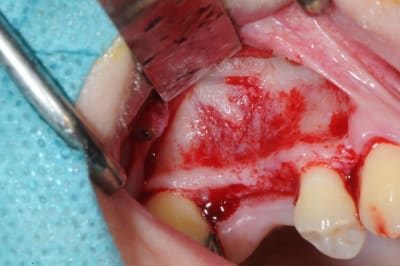

les premières photos, c'était ouverture par voie latérale

les suivantes;

- forage et transperçage de la crête sans aller trop loin...

- essayage pilier pour parallélisme

- forage à 3mm

- visualisation de la hauteur sous la membrane de Schneider

- utilisation d'un ostéotome diamètre 3.4 puis 3.8

(sous dimensionnement de diamètre par rapport à l'implant prévu :4mm)